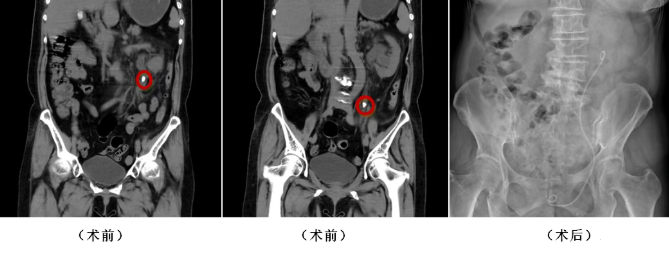

患者张先生(化名)左侧腰腹部疼痛20余天,检查提示左侧输尿管盆段结石伴肾积水、感染,同时合并高血压、前列腺增生、颈动脉斑块等多种基础疾病,手术风险更高。张宝主任团队术前全面评估患者心肺功能及基础疾病,制定个性化麻醉与手术方案,在全麻下为其实施经尿道输尿管镜激光碎石术,高效清除结石后留置支架管。术后通过抗感染、补液、解痉止痛等对症治疗,患者病情平稳,自主排尿恢复良好,各项指标逐步回归正常,顺利出院。